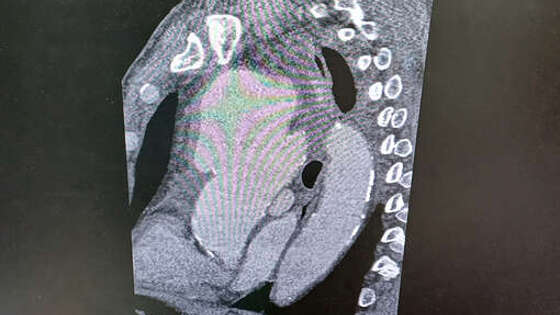

Врачи Рязанского кардиодиспансера спасли 50-летнего мужчину с гигантской аневризмой аорты. Об этом сообщили в пресс-службе регионального министерства здравоохранения. Пациент из Касимовского района попал в учреждение после осмотра врачом-кардиологом Кариной Агаян в "Поезде здоровья". Врача обеспокоил приступообразный кашель, который усиливался, когда мужчина ложился. На скорой пациента доставили в кардиоцентр. Медики отметили, что "в организме мужчины, фактически, находилась мина замедленного действия, которая в любой момент могла разорваться". "Компьютерная томограмма подтвердила выпячивание аорты размером 9 на 9 сантиметров. Гигантская мешотчатая аневризма, больше, чем гусиное яйцо", - рассказал заведующий отделением N5 Рязанского кардиодиспансера Сергей Загородний. По словам специалиста, аневризма сдавливала все близлежащие органы и ткани: трахеи, бронхи, верхнюю полую вену. После детальной диагностики медики направили пациента в научный центр хирургии им. академика Б.В. Петровского в Москве, где врачи провели операцию на открытом сердце - иссекли участок с аневризмой, установили протез. Вмешательство прошло успешно.